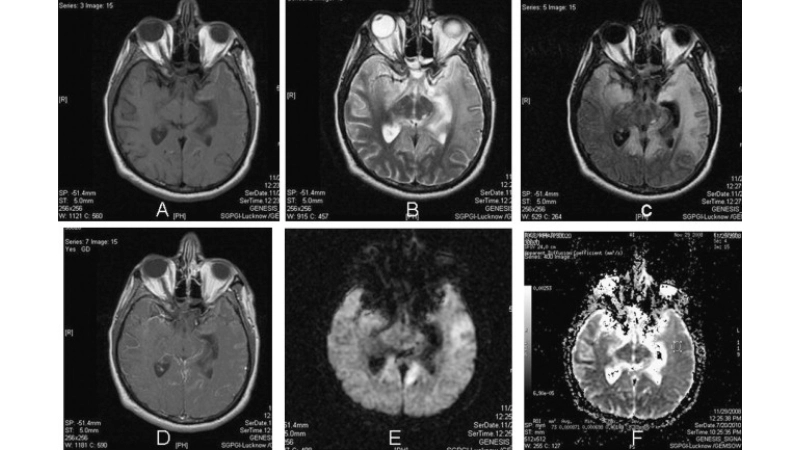

Image description of Murray Valley Encephalitis

Murray Valley Encephalitis is a rare but serious viral infection transmitted by mosquitoes, primarily affecting the brain and nervous system, with potential life-threatening complications.